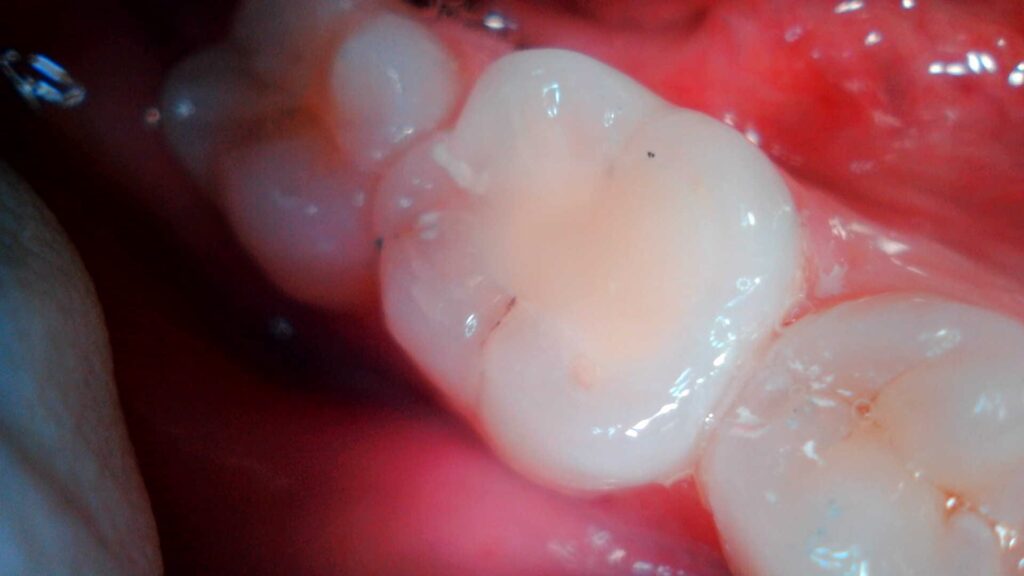

La Endodoncia limpia y conforma el interior de los conductos de las raíces dentales, sellándolos posteriormente impidiendo así la presencia de microorganismos en ellos. De este modo se consigue conservar el diente sin tener que extraerlo y la recuperación, en la mayoría de los casos, de la infección a nivel óseo.

El propósito principal de la Odontología es preservar todas las piezas dentales, ya que un diente natural no puede ser superado por ningún implante artificial.